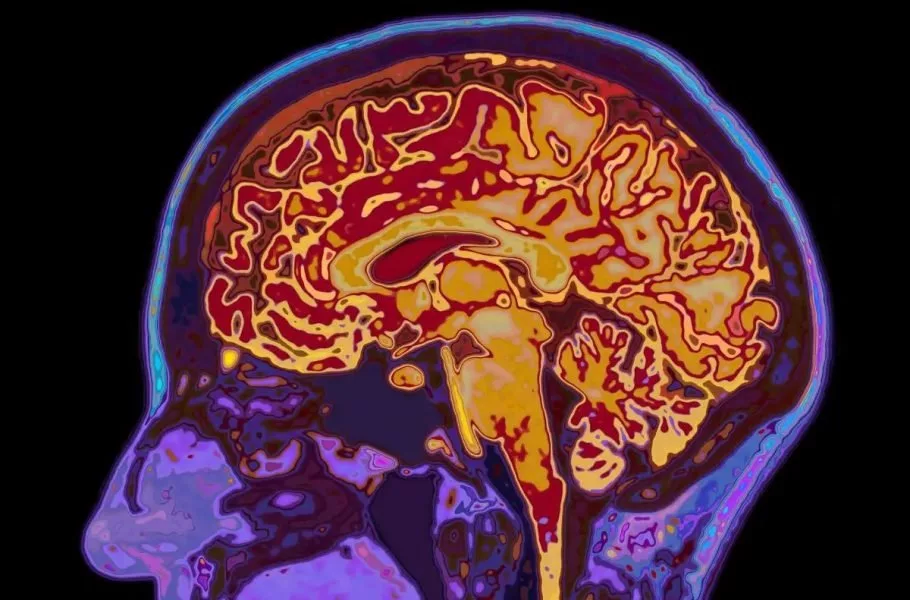

شوک علمی: مغز انسان تا ۳۲ سالگی کامل نمیشود

شاید فکر کنید با تمامشدن دوران نوجوانی، مغز شما هم به بلوغ و رشد نهایی رسیده است. اما دانشمندان دانشگاه کمبریج این باور قدیمی را رد کردهاند. آنها با اسکن مغز ۴ هزار نفر (از نوزاد تا ۹۰ ساله) کشف کردند که مغز انسان نه یک مسیر خطی، بلکه ۵ دوران متمایز را طی میکند. محققان میگویند مغز ما تازه در اوایل دهه ۳۰ زندگی وارد فاز بزرگسالی میشود.

تصور رایج این است که نوجوانی در ۱۸ یا ۱۹ سالگی تمام میشود، بااینحال مطالعه جدید نشان میدهد که مغز تا حدود ۳۲ سالگی همچنان در فاز «نوجوانی» باقی میماند. در این دوران طولانی (از ۹ تا ۳۲ سالگی) مغز مشغول سیمکشی مجدد و افزایش بهرهوری است. این همان زمانی است که بیشترین خطر بروز اختلالات سلامت روان وجود دارد، زیرا مغز درحال تغییرات بنیادین است.